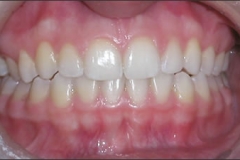

This mouth had recession on just one tooth with very little bone to support the tooth. The area needed support and thickness. The tissue was placed and the area now has thicker tissue to withstand the forces that the patient needs to place on it.